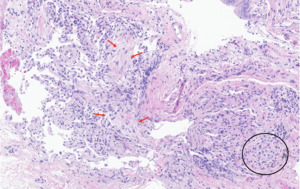

Eighteen days after discharge, he presented to oncology clinic with recurrence of dyspnea and cough. A pleural effusion and interval increase in the right-sided lung opacities were found on CXR (Figure 1B), and he was prescribed a 5-day course of levofloxacin for CAP. His symptoms persisted, and, on day 5 of levofloxacin, he was readmitted to the hospital after a repeat CXR demonstrated a right-sided hydropneumothorax (Figure 1C). He continued to have normal vital signs and oxygen saturation, and his physical exam demonstrated coarse crackles throughout the right-sided posterior chest fields. A chest tube was placed (Figure 2A) with pleural fluid analysis showing >15,000 nucleated cells per microliter, 48% granulocytes, 5% lymphocytes, and 2% eosinophils. Although the right lung re-expanded on subsequent CXRs, he had persistent right-sided lung opacification and dyspnea on exertion after 3 days of broad spectrum antimicrobial therapy, which led to bronchoalveolar lavage (BAL) and transbronchial biopsy. BAL showed 435 nucleated cells per microliter with 73% lymphocytes, 11% granulocytes, and 2% eosinophils. No malignant cells or organisms were demonstrated in either pleural or BAL fluid. Transbronchial biopsy of the right middle lobe demonstrated minimal inflammatory changes of the interstitium and airways and a possible focus of fibroblastic tissue consistent with organizing pneumonia (Figure 3).

In addition to diversity in the temporality of ICI pneumonitis’ presentation, there is also diversity in the radiographic presentation. On chest computed tomography (CT) scans, radiographic findings similar to organizing pneumonia, nonspecific interstitial pneumonia, hypersensitivity pneumonia, acute interstitial pneumonia, and sarcoid-like granulomatosis have all been described.6 One group stratified ICI pneumonitis into early- and late-onset subtypes in order to study potential clinical and radiographic differences.6 Patients with early-onset ICI pneumonitis (within 6 weeks of therapy) had more severe symptoms, poorer prognosis, and, more frequently, an organizing pneumonia-like radiographic pattern.6 In contrast, patients with late-onset ICI pneumonitis (>6 weeks of therapy) had fewer symptoms, better prognosis, and NSIP-like findings as the dominant radiographic pattern.6 Histopathologic findings in ICI pneumonitis are not as well characterized as the radiographic features. The most common reported pathologic finding is organizing pneumonia, followed by other non-specific inflammatory changes such as vague airspace granulomas, foamy pneumocytes, airspace macrophages, and interstitial inflammation.1,8,9 Rare reports of diffuse alveolar damage and acute fibrinous pneumonitis are associated with worse outcome and death.9